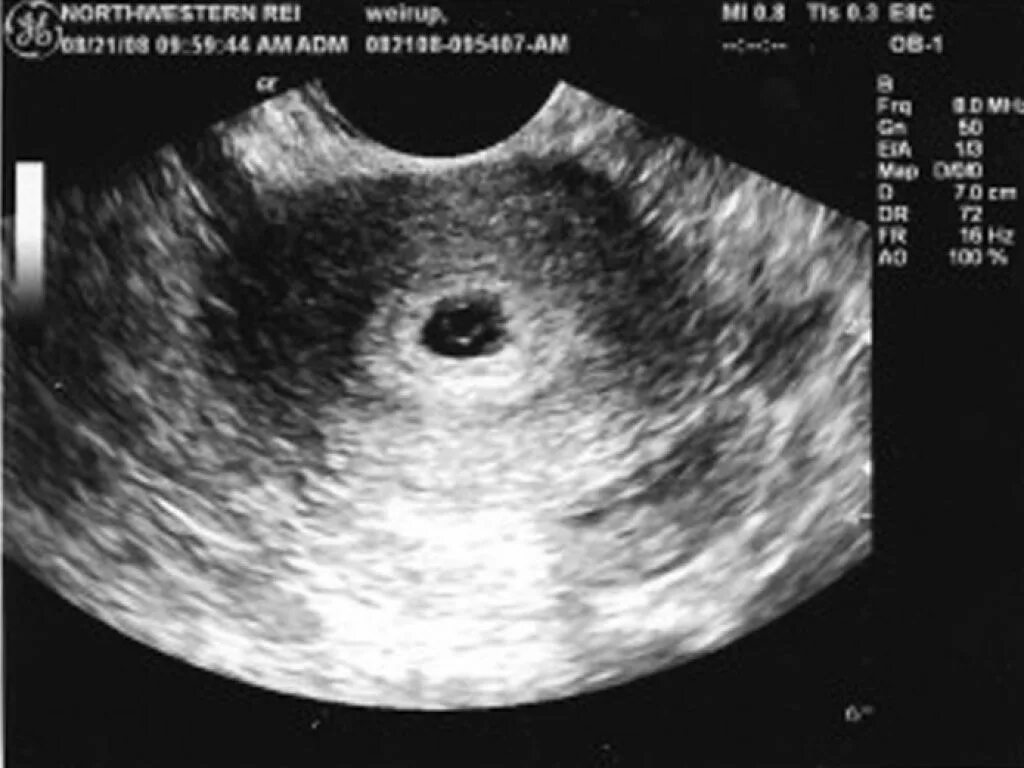

Эмбрион в матке после зачатия